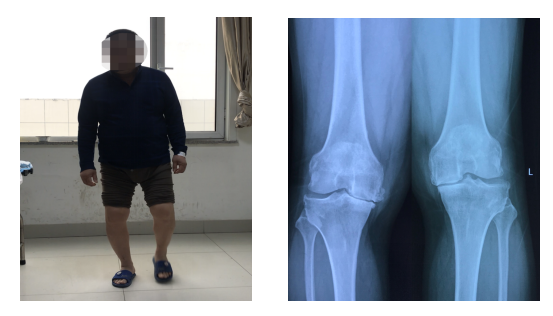

聊城市中医医院国医楼骨关节科门诊里,东昌府区朱老庄镇的张大爷,紧紧地握着刘刚主任的手说:“感谢刘主任和关节科各位大夫护士,把我的两个膝盖治好了,不光治好了我多年的罗圈腿,腿变直了,更没想到的是,两次手术以后,我竟然没怎么疼,早知道这样,我早几年就来了,就是害怕,白白在家受了这几年罪啊,今天我出院了,专门来感谢你们!”。这是出现在我院骨关节科里医患互动的一幅感人画面,也是骨关节科将快速康复理念应用于髋膝关节置换患者管理后取得良好效果的真实印证!

我院骨关节科自2016年率先将加速康复理念(ERAS)应用于髋膝关节置换患者围手术期的管理当中。我院于2021年被国家卫健委纳入加速康复外科第二批骨科试点医院。骨关节科在工作实践中结合中医药优势,创新思路、拓宽渠道,不断总结完善提高,目前已形成特色突出的髋膝关节置换快速康复流程,为广大关节置换患者带来了福音。 将加速康复外科理念融入到髋膝关节置换患者的康复过程中,能有效降低患者术后疼痛、血栓、感染、贫血等并发症和不良反应发生率,使患者手术后无痛、无应激反应,提高患者康复过程的舒适度,加速患者康复,提高临床疗效。 为此我院骨关节科专门制定了具有中医特色的髋膝关节快速康复流程及患者康复指导宣传手册。设定了髋膝关节置换快速康复“十无”目标:无痛、无血栓、无出血、无感染、无肿胀、无引流管及尿管、无止血带、无呕吐、无应激、无风险。 对每一台关节置换手术,骨关节科都要进行晨间术前讨论,针对患者适应症的选择是否合适,有无需要治疗的内科疾病,预计手术操作中会遇到的问题和需要注意的要点,进行详细的讨论,做好周密的手术规划,为手术的成功奠定基础。 骨关节科针对每一例髋膝关节手术患者,在病人入院起,即进入康复流程。 术前对患者进行疼痛及关节功能评分,指导患者术前学习功能锻炼方式,口服止痛药物超前镇痛,术中关节周围软组织封闭、术后给以静脉及口服止痛药物、镇痛药微量泵、耳穴压豆、外用冷疗等多模式镇痛措施。术后给于口服三七粉活血止血,指导患者行踝泵及股四头肌功能锻炼、行下肢足底泵治疗预防血栓,腹部灸疗及穴位贴敷缓解术后胃肠道反应,等等一系列具有中医特色的快速康复治疗措施。 骨关节科行髋膝关节置换患者,术后第一天即在主管医师的指导下,下地行功能锻炼。主管医师每天都要对患者进行功能锻炼的指导和沟通,针对患者康复过程中遇到的问题,给与耐心细致的讲解,缓解患者心理压力,鼓励患者积极康复锻炼。 百舸争流,奋楫者先;千帆竟发,勇进者胜。骨关节科坚持定期开展髋膝关节置换相关知识的集中学习,通过学习国内知名专家的讲座,查找问题,总结经验,不断提升理论技术水平。骨关节科每周六晨间交班后,都要进行关节置换术后影像点评,总结经验,在不断探索中创新,在反复实践中提升,通过多种形式的学习、交流,使骨关节科手术理念、手术方式都紧跟学术前沿,努力追求打造髋膝关节置换快速康复流程“十化”,即规范化、标准化、精准化、数字化、个性化、微创化、透明化、流程化、差异化、智能化。 骨关节科全体医护人员将本着精益求精的专业精神,坚持以病人为中心的服务理念,为每一位髋膝关节置换患者提供安全、优质的医疗服务,使患者安全、舒适地度过围手术期和功能康复期,使病人快速康复,优质康复,让病人在治疗康复过程中感到舒适和满意! 骨关节科:聊城市中医医院国医楼六楼 电话:8341447/8341448 供稿|刘晓之(骨关节科)